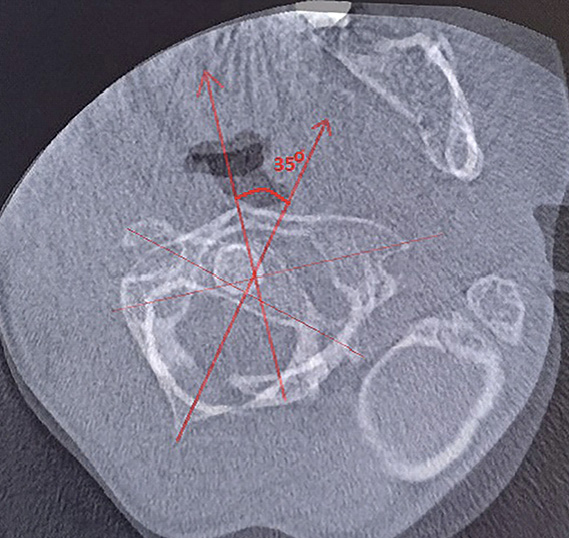

Для уточнения характера выявленных изменений в ручном режиме с помощью программы Adobe Photoshop© выполнено наложение аксиальных срезов 1-го и 2-го шейных позвонков, полученных по отдельности, с созданием единого изображения с возможностью комплексной оценки взаимоотношений изучаемых сегментов (рис. 2). При анализе смоделированного изображения обнаружено, что ротация атланта составляет 35° вправо (рис. 3). Суставные поверхности латерального атлантоаксиального сустава справа совпадают, а слева –суставная поверхность атланта смещена кпереди, что соответствует ротационному подвывиху типа II по классификации J. W. Fielding и R. J. Hawkins [8].

Рис. 2. Конусно-лучевая компьютерная томография краниовертебральной области. Аксиальные срезы на уровне аксиса (А) и на уровне атланта (Б). Стрелками обозначены передне-задние оси позвонков

Рис. 3. Наложение изображений А и Б, представленных на рис. 2. Определение угла ротации атланта